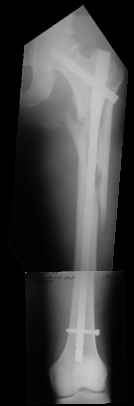

I choose Long Gamma Nailing and did it on 24.1.2006.

Now posting the post op x-rays for all of yours comments please. Don't hesitate to criticize me.

Congratulations. Virtually perfect. What reduction technique did you use? Looks like still traction table? To cavil to at least something looks like reduction is in microscopic varus - comparative x-rays can clear this - though only for academic interest with no clinical significance. Did you insert distal screws?